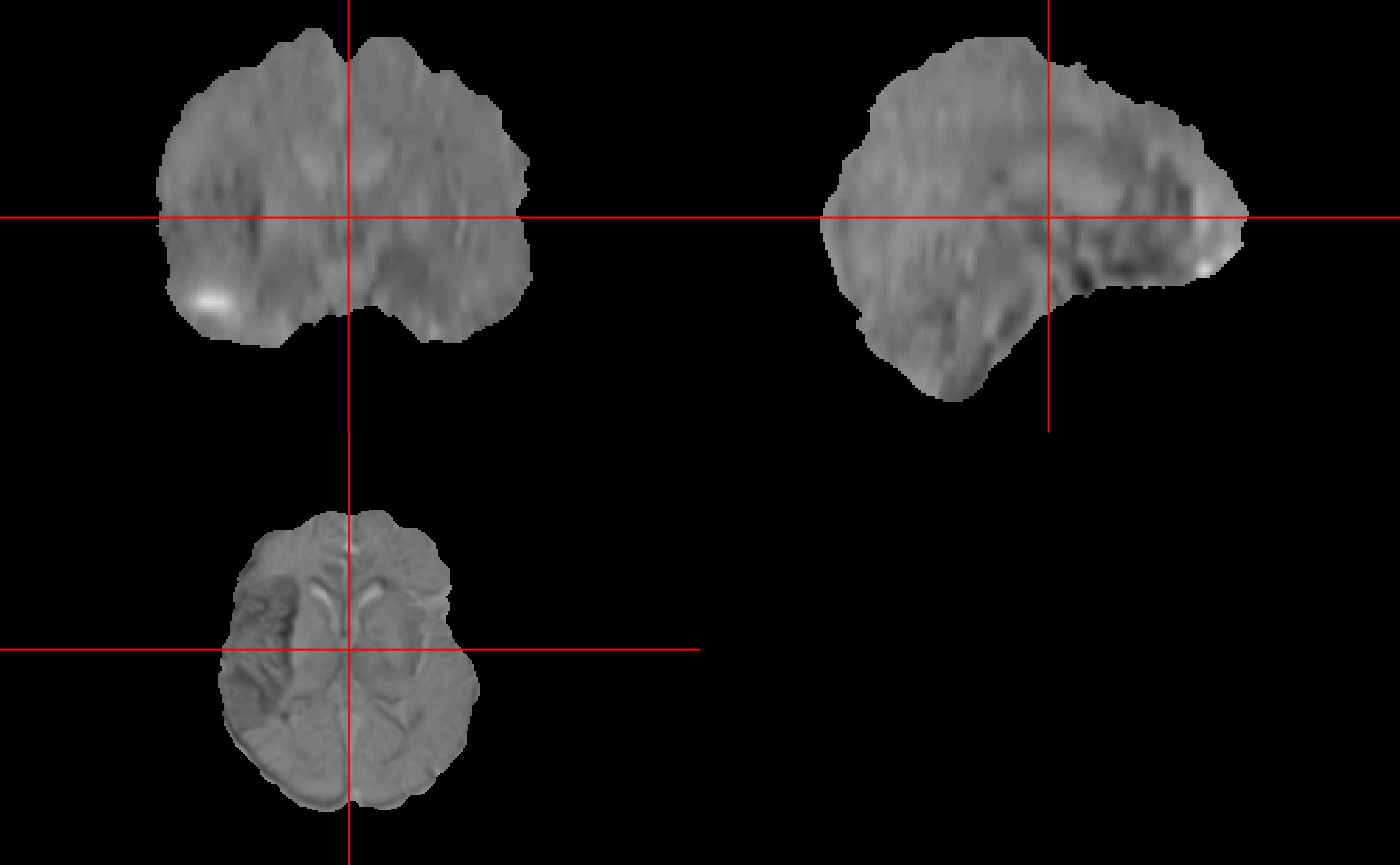

Now we can visualize the score images